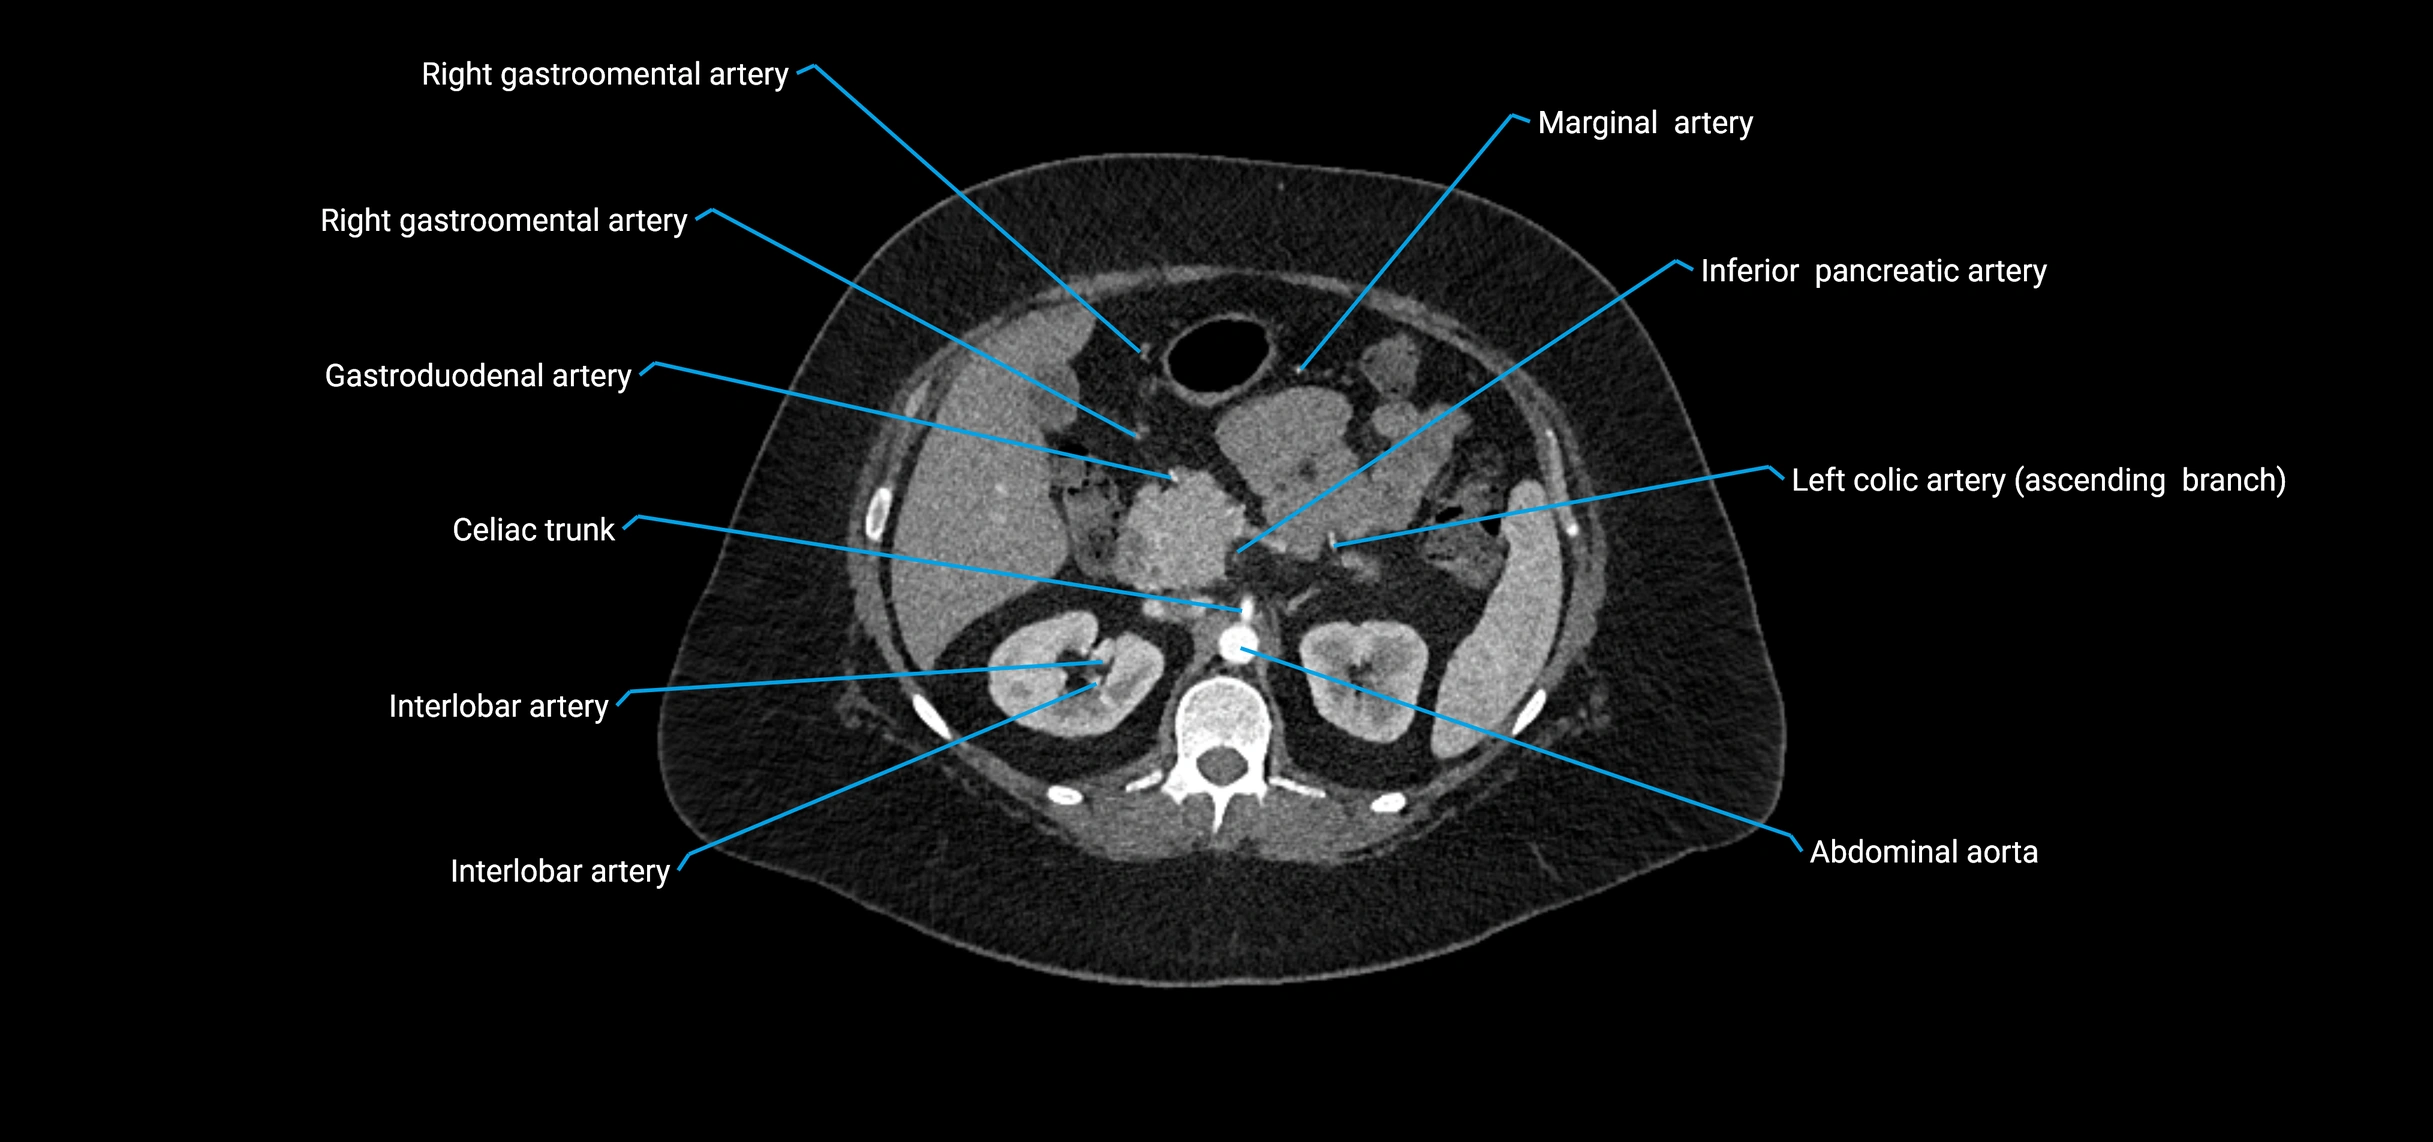

Contrast-enhanced CT (CTA):

• Gold standard for abdominal aortic imaging

• Provides excellent detail of lumen, wall, aneurysm, thrombus, and branch vessels

• Multiplanar and 3D reconstructions help in aneurysm measurement, stent graft planning, and dissection evaluation

• Detects acute rupture, traumatic injury, or occlusion with high sensitivity